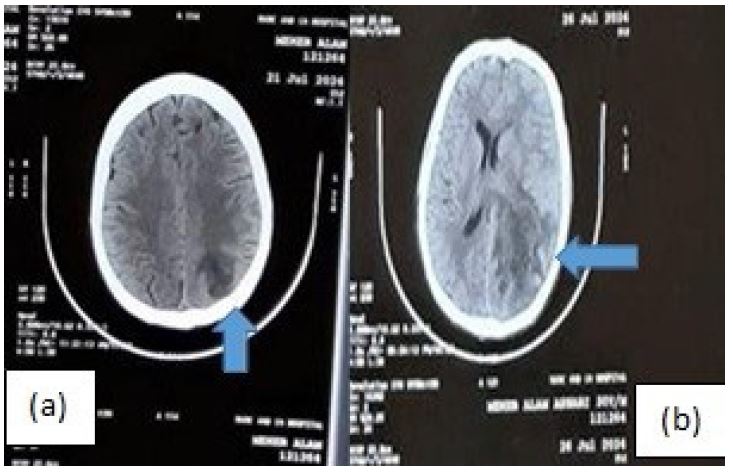

Figure 3: (A) NCCT (day 19) head showing ill-defined hypodense lesion in left parieto-occipital area with hemorraghic foci. (B) NCCT Head (day 23) showing left subacute infarct with haemorrhagic transformation with mass effect and MLS of 8.7 mm.

On day 19, the patient developed altered behavior, followed by a Generalized Tonic-Clonic Seizure (GTCS) and was found have developed ischemic infarct with hemorrhagic foci (Figure 3a). A 2D echocardiogram, and lower limb Doppler showed no evidence of thrombus. Following the exclusion of papilledema Cerebrospinal Fluid (CSF) analysis was done which did not reveal any evidence of CMV meningoencephalitis. The patient was managed conservatively with antiedema measures and antiepileptic medication. Subsequently, the patient developed right-sided hemiparesis (NIHSS score of 10), with repeat CT scan showing extension of the infarct with mass effect and a midline shift of 8.7 mm (Figure 3b). Despite maximum medical efforts the patient succumbed to the illness.